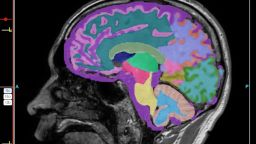

Неврологическое заболевание, называемое хронической травматической энцефалопатией, или ХТЭ, чаще всего диагностируется у людей, которые подвергались многократным ударам по голове во время занятий контактными видами спорта, и теперь появились доказательства наличия у него генетических повреждений внутри мозга.

Исследователи изучили мозг футболистов и других людей с этим редким неврологическим заболеванием, и обнаруженные ими генетические повреждения оказались схожими с теми, что наблюдаются в мозге людей с болезнью Альцгеймера. Повреждения были настолько обширными, что их можно сравнить с сотнями лет старения.

На данный момент у ученых нет простого анализа крови или сканирования, которые могли бы обнаружить ХТЭ. У живого человека. Единственный способ поставить точный диагноз — взять тонкие срезы мозга после смерти и с помощью микроскопа обнаружить аномальное накопление тау, белка, стабилизирующего определённые элементы мозга. Избыток тау может повредить кровеносные сосуды и клетки мозга, и это накопление также является отличительным признаком. болезни Альцгеймера.

Мозг состоит из мозаики клеток, каждая из которых имеет свой собственный геном. Каждое деление стволовой клетки приводит к накоплению мутаций. В новом исследовании использовались недавно появившиеся технологии секвенирования и амплификации для изучения генов отдельных клеток сотен нейронов префронтальной коры — области мозга, отвечающей за принятие решений и другие мыслительные способности.

Исследователи сравнили результаты четырех групп: 15 человек, которые получили повторные удары по мозгу и у которых была диагностирована ХТЭ; четыре человека, которые получили повторные травмы головы, но у которых не развилась ХТЭ; 19 человек без истории черепно-мозговых травм или признаков ХТЭ; и семь человек, у которых была болезнь Альцгеймера.

У людей с ХТЭ в клетках были обнаружены геномные повреждения, похожие на те, что наблюдаются у людей с болезнью Альцгеймера. У людей с повторными травмами мозга, но без диагноза ХТЭ, подобных повреждений не наблюдалось.